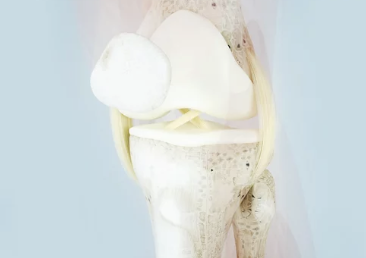

십자인대 파열은 무릎 관절의 안정성을 담당하는 중요한 인대 중 하나인 전방 십자 인대(ACL)가 손상되는 부상입니다. 이러한 부상은 스포츠 활동 중에 흔히 발생하며, 갑작스러운 방향 전환, 정지, 또는 점프로부터 착지하는 동작에서 주로 발생합니다. 십자인대 파열의 주요 증상으로는 부상 당시 무릎에서 '팝'하는 소리가 들리는 것, 심한 통증, 부기, 무릎의 불안정성 및 움직임 범위의 감소가 있습니다. 특히, 무릎에 체중을 싣거나 걸을 때 통증이 심해지는 것이 특징입니다. 십자인대 파열은 MRI와 같은 영상 진단을 통해 확인할 수 있으며, 치료 방법은 부상의 정도와 환자의 활동 수준에 따라 보존적 치료 또는 수술적 치료가 고려될 수 있습니다. 십자인대 파열은 적절한 치료와 재활을 통해 회복이 가능하지만, 전문적인 의료진의 진단과 치료 계획이 필요한 중대한 부상입니다.

십자인대 수술은 무릎의 안정성을 회복하고 손상된 십자인대를 복구하기 위해 시행되는 수술입니다. 이 수술은 주로 스포츠 활동 중에 발생한 심각한 무릎 부상을 치료하기 위해 사용됩니다. 십자인대는 무릎 관절의 중요한 부분으로, 무릎의 전방과 후방을 안정시키는 역할을 합니다. 십자인대가 파열되면 무릎의 안정성이 떨어지고, 활동에 제한을 받게 됩니다.